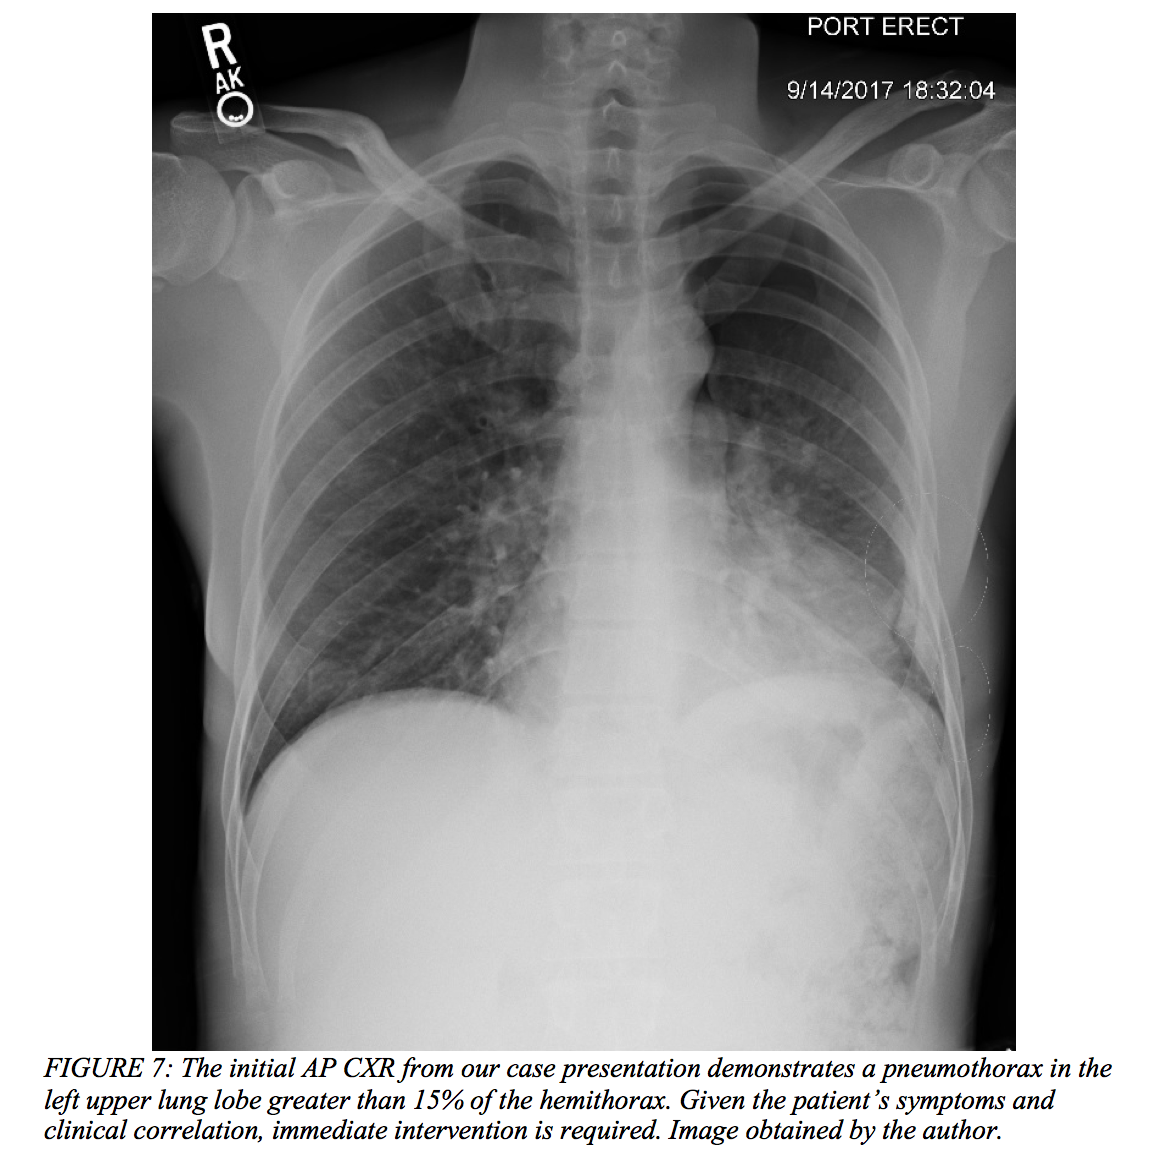

Case Conclusion

After initial imaging displayed a pneumothorax (Figure 7 above), our 39-year-old male had a pig-tail catheter placed successfully (Figure 8 below). However, his dyspnea failed to improve, and he continued to desaturate even when connected to supplemental oxygen via non-rebreather. The decision was made to replace the pig-tail catheter for a 28-French chest tube (Figure 9). His clinical status failed to improve even after this intervention, and he ultimately required intubation due to impending respiratory failure and an evolving pulmonary contusion. The patient was then transferred to the surgical intensive care unit and closely monitored on mechanical ventilation for two weeks. His oxygenation and ventilation improved over time, and he was extubated and subsequently discharged without any further complications.